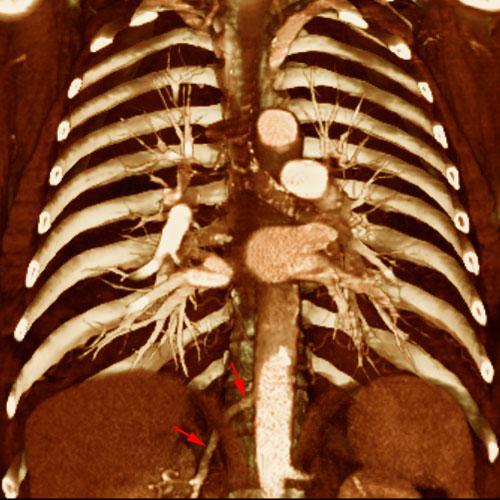

Arterias renales polares